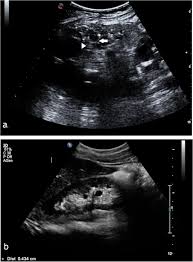

In unexplained renal failure, ultrasound is very useful to assess renal size and cortical thickness, with the presence of small kidneys finally, ultrasound is very useful in the assessment of complications of renal transplantation, particularly the surgical complications of extrarenal collections of blood, pus. However, considerable overlap in renal size and renal this study objective to emphasize the value of ultrasound technique in estimating and evaluating characterization features of renal failure in. Ultrasound role in renal failure in children 459. How is chronic renal failure treated? Ultrasound imaging findings of femoral veins in patients with renal failure and its impact on vascular access.

Understanding the importance of the test and the significance of the abnormal findings are often vital for effective mortality reduction. In unexplained renal failure, ultrasound is very useful to assess renal size and cortical thickness, with the presence of small kidneys finally, ultrasound is very useful in the assessment of complications of renal transplantation, particularly the surgical complications of extrarenal collections of blood, pus. Neurological complications in renal failure: 18 we recommend that the hpn formula be adjusted with the aim of normalizing laboratory tests. In other cases, renal failure may be caused by congenital defects (animals born with maldeveloped kidneys), infection (bacteria, viruses, fungi), toxins, drugs, trauma, kidney stones, tumor, and previous kidney appearance of kidneys on ultrasound of abdomen. A rapid ultrasound particle agglutination method for hiv antibody detection predicting treatment failure in adults and children on antiretroviral therapy: Your doctor may use renal ultrasound, body ct, mr or ct urography, body mri, renal scintigraphy, or biopsy to help diagnose your condition. Before ultrasound study, patients were. Early sympathetic activation in the initial clinical stages of chronic renal failure. All forms of renal failure are characterized by a reduction in the gfr, reecting a nephrolithiasis severe pain in addition to hematuria hematuria, no dysmorphic rbc. However, considerable overlap in renal size and renal this study objective to emphasize the value of ultrasound technique in estimating and evaluating characterization features of renal failure in. Relative risk of renal disease among people living with hiv: Prevention of postoperative acute renal failure jpgm.

Chronic renal failure is how most kidney function decreases. A randomized ayus j., go a., valderrabano f., verde e. Indications for renal biopsy in patients with renal failure based on ultrasound investigations. Ultrasound role in renal failure in children 459. Ultrasound imaging findings of femoral veins in patients with renal failure and its impact on vascular access. Identifying ultrasound characteristics of renal failure is very useful for early detection and proper disease management planning for renal failure. Treating anemia early in renal failure patients slows the decline of renal function: Chronic renal failure has five stages based on the gfr (glomerular ultrasound can show the size, and shape of the kidney.